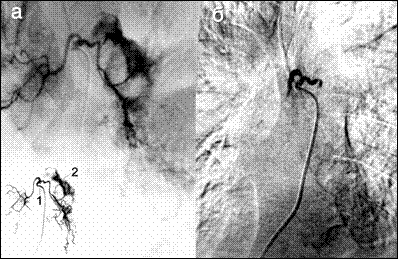

Клинические проявления легочного кровотечения зависят от его интенсивности. При кровохаркании (1 степень) состояние больного, как правило, не страдает. При массивном и, тем более, профузном кровотечении кровь поступает полным ртом, пациент не успевает ее откашливать, быстро появляются признаки дыхательной недостаточности из-за аспирации геморрагической жидкости в бронхи здорового легкого, развивается асфиксия. Топическая диагностика источника кровотечения (сегмент, доля, легкое), возможна только при проведении неотложной трахеобронхоскопии. Кровоточащий сосуд устанавливается после проведения бронхиальной артериографии (рис. 9).

Рис. 9. Бронхиальные артериограммы. а – на высоте кровотечения, б – после эндоваскулярной окклюзии бронхиальных артерий. 1 – катетер в устье общего бронхиального ствола, 2 – экстравазация контрастированной крови в паренхиму легкого.